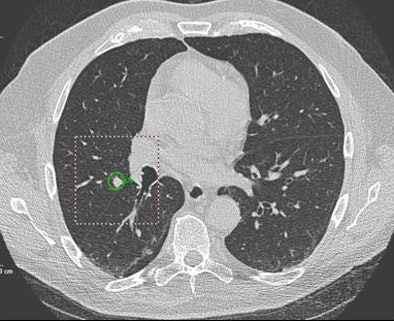

| Solid nodule of 6 mm in right lower lobe was a false negative, found by the radiologist but not marked by CAD. |

Most (13/28) false negatives were pleura-based, and were more prevalent in the right lung (n = 19) than the left lung (n = 9), with an average size of 9 mm.